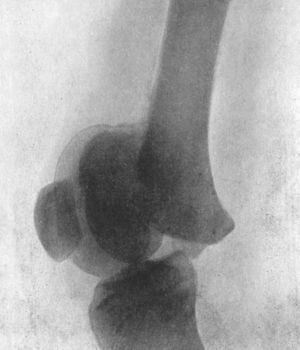

99.Radiogram of Backward Dislocation of Ankle195

100.Compound Dislocation of Talus197

101.Radiogram of Fracture-Dislocation of Talus198